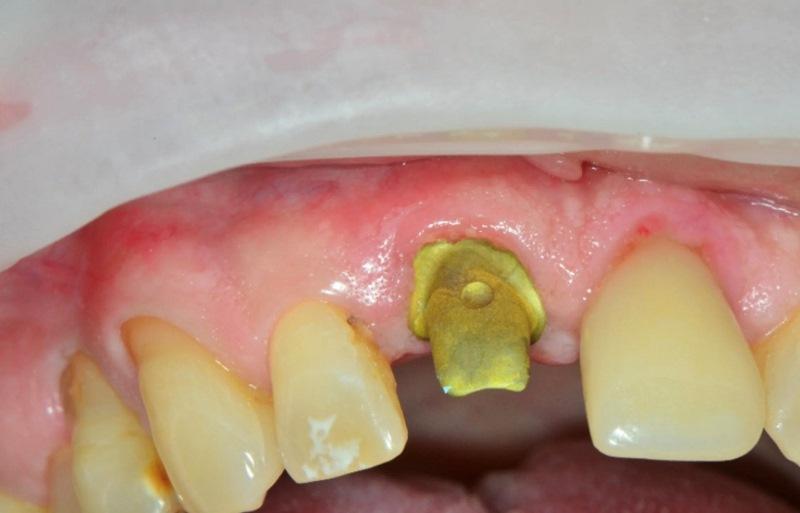

Пациент, мужчина 78 лет, обратился на консультацию по поводу перелома правого верхнего центрального резца (зуб 1.1) (Фото 1). Он пользовался временным частичным протезом для замещения коронки зуба. Пациент выразил желание заменить зуб имплантатом. При изучении анамнеза значимых соматических заболеваний не выявлено.

Фото 1. Пациент обратился с переломом правого верхнего центрального резца (зуб 1.1) на уровне десны.